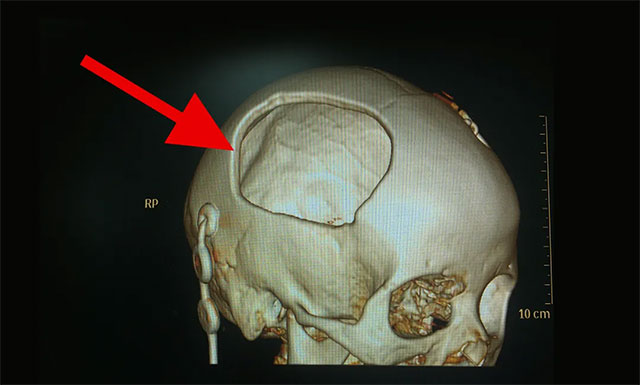

▲ 顱骨大塊缺損,腦組織凹陷嚴(yán)重

隨后,鑒于患者病情已穩(wěn)定,其右側(cè)顳頂骨大塊缺損,大小約為7厘米X 6厘米,腦組織失去了支撐和保護(hù),且其顱骨缺損的時(shí)間愈長(zhǎng),顱骨缺損綜合征及繼發(fā)性腦損害的發(fā)生率愈高。因此,今年2月24日對(duì)其進(jìn)行了PEEK顱骨修補(bǔ)術(shù),以便更好地保護(hù)腦組織,避免了患者因顱骨缺損而引起的各種健康問(wèn)題和額外風(fēng)險(xiǎn)。